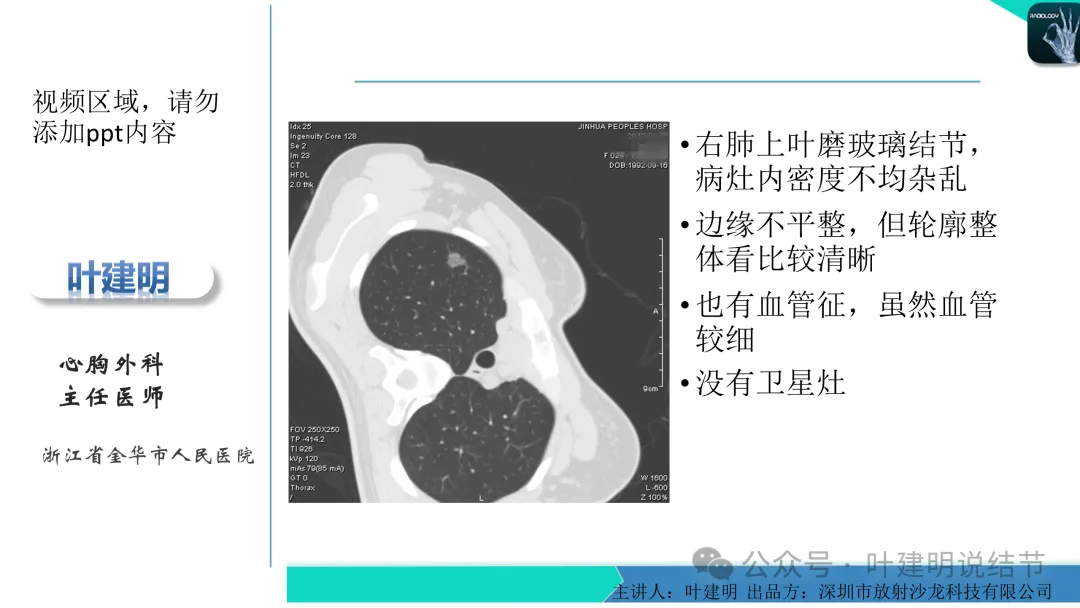

早在2020年时,我受邀在《放射沙龙》做过一个系列的精品课,当时专门总结分析过各类良恶性肺结节与肿块的影像特征,这是当时关于微浸润性腺癌影像特征的分析,今天看来仍基本不太需要改变,大家有兴趣的可以参考: